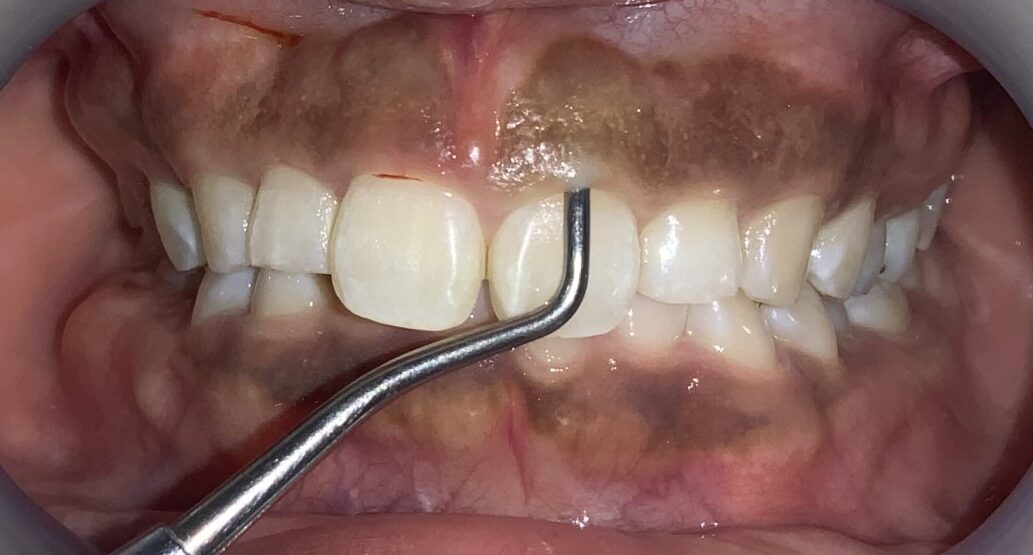

隣の歯も同じように検査します。

隣の歯は前歯ほどではないですが、しっかりと歯ぐきが、かぶっています。

この歯は犬歯です。犬歯もたくさんの歯ぐきに覆われているようですが、治療をする場合には注意が必要です。

犬歯はあまり大きくすると、八重歯のように見えてしまい、せっかくの治療が台無しになる場合があります。また、被っている歯ぐきがたくさんあっても、歯ぐきが薄い場合があり、このような歯ぐきの場合は、治療後に歯ぐきが退縮してしまい、歯槽膿漏の歯ぐきのように見えてしまう場合があります。